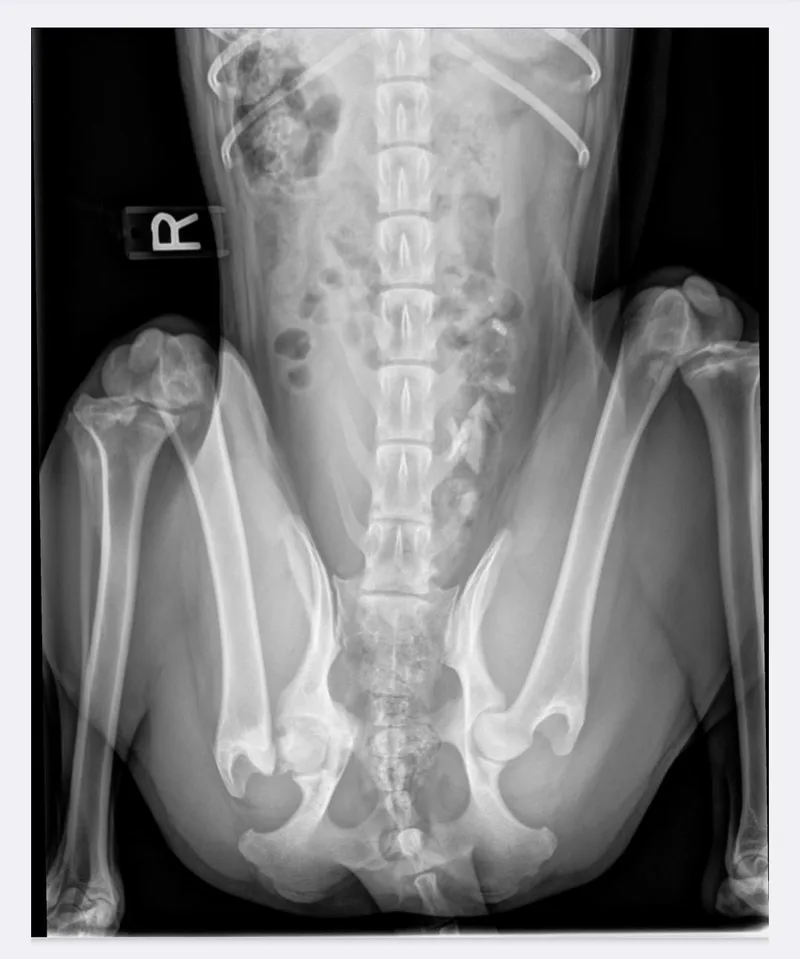

Robyn is a sweet, young border collie mix that came to a shelter as a stray with a limp. We were asked to help since the shelter was unable to pay for the potential treatment needed. We stepped in and got Robyn seen by an orthopedic vet who took x-rays and found an old broken right hip injury. Robyn’s body had scarred over the break, providing enough stabilization that she could walk and run with barely any noticeable limp. While in foster care, she mis-stepped getting out of the truck and fully broke off the ball of the femur (the part that goes into the hip socket). Robyn had emergency surgery to clean up the end of the broken bone, a procedure similar to an FHO (femoral head ostectomy). When she heals, Robyn’s body will scar around the hip to provide the stabilization needed for her to run and play again without pain. Will she be able a contender for the AKC agility championships? Probably not. But she can still be an active and playful dog who can live a full life. For now, Robyn will need additional veterinary follow-up visits (paid for by WBCR) until she is fully cleared from the vet. There are also physical therapy exercises that her adopter will need to perform on her at home and adhere to exercise restrictions for at least the next couple months. Robyn is a sweetheart and who knows what all she has been through in just her first year of life! But now she is on the mend and ready for a home that can show her all the good things life has to offer! Robyn can be slow to warm to people. She is not aggressive, just shy. She is curious and will come up for a quick greet but doesn’t necessarily stick around for attention. She does enjoy playing interactive games with her human though, like a good game of fetch! She may never be a cuddler or your constant shadow and can be aloof. She enjoys her alone time, lounging outside or in her kennel by herself. Robyn has not been tested with children under 12 yrs of age but is gentle with greetings and in play around people. She can be playful with other dogs her size and even romped around at the WBCR reunion! She has not met dogs of other sizes or cats yet. She enjoys interactive games with her human- a fun game of fetch or throwing stuffies around. She walks fairly well on leash, but can pull sometimes. Once Robyn is off medical restrictions, we’ll have to see what her exercise drive is like. Before surgery, she was a medium energy dog where a walk and off-leash play time kept her happy. Are you looking for a moderate energy dog who is unlike most border collies that need your constant attention? And are you someone who has experience helping a dog recover from an orthopedic procedure (or willing to learn)? Robyn will be available towards the end of January/early February and is looking for her perfect match! Due to our small volunteer team, we can’t respond to inquiries to this listing. To learn more about this dog and our adoption process or to apply, visit wbcrescue.org. Thank you for considering adoption!